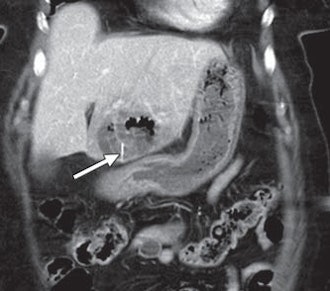

The remaining three patients presented with abdominal pain and underwent CT scans. In two patients, the wire perforated the small intestine. The metal piece perforated through the stomach and into the liver of the third patient and was surrounded by a large hepatic abscess. Laparoscopy was performed on the basis of the CT and clinical findings, and the bristle was removed through surgery.